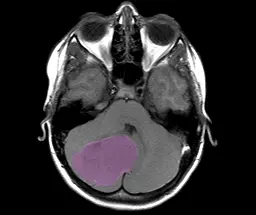

MRT-Image of a Medulloblastoma

Medulloblastoma is a malignant tumor of the cerebellum. Medulloblastoma can occur at any age, but it most commonly affects children. Medulloblastomas are classified in four distinct molecular-biological subgroups that are characterized by widely varying disease courses and chances of cure. Tumors of groups 3 and 4 are particularly common in children. However, little is understood up to know about these two types. Therefore, treatment of cancers of this group is often very difficult. “Even if patients respond well to the treatment, their cancer is often being cured at high costs, because the therapy can have negative effects on the brain, the IQ and the children's further development,“ said Stefan Pfister from the German Cancer Research Center (Deutsches Krebsforschungszentrum, DKFZ), who is also the director of the Hopp Children's Tumor Center at the NCT* Heidelberg (KiTZ) and pediatric oncologist at the Heidelberg University Hospital.